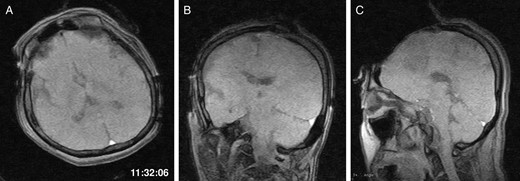

General anaesthesia was induced. Following left frontal craniotomy and dural incision, the first iMRI was performed (Fig. 1 ). One hundred fifty-eight minutes from induction, the patient regained consciousness after all anaesthetics were ceased. Tumour resection was performed with free conversation. However, after 143 min of surgery under the awake condition, the patient came to complain of excessive sleepiness though she could respond to verbal commands. Electrocorticogram (ECoG) did not detect after-discharge. The tumour was successfully removed en bloc fashion. Progressive brain swelling was not observed. The second iMRI was commenced 182 min into the awake phase (Fig. 2). Thirteen minutes from the beginning of the second iMRI scanning, the patient did not respond to noxious stimuli. When the patient was removed from the gantry, she was unconscious and had stopped spontaneous breathing. Her pupils were isocoria and did not dilate. Neither epileptic seizure nor anaphylactic reaction occurred. The peripheral oxygen saturation was not measurable, but cardiac instability or signs of vomiting were not observed. We decided to discontinue the operation under the awake status. No electrolyte imbalance or hypoglycaemia was observed. Subsequently performed iMRI identified a thin subdural haematoma in the contralateral side (Fig. 3). The fourth iMRI confirmed that most of the haematoma was evacuated following right frontal craniotomy.

The first intraoperative magnetic resonance images performed after the craniotomy. (A) Axial, (B) coronal and (C) sagittal T1-weighted scout images show the left frontal tumour. The time of scan is superimposed.